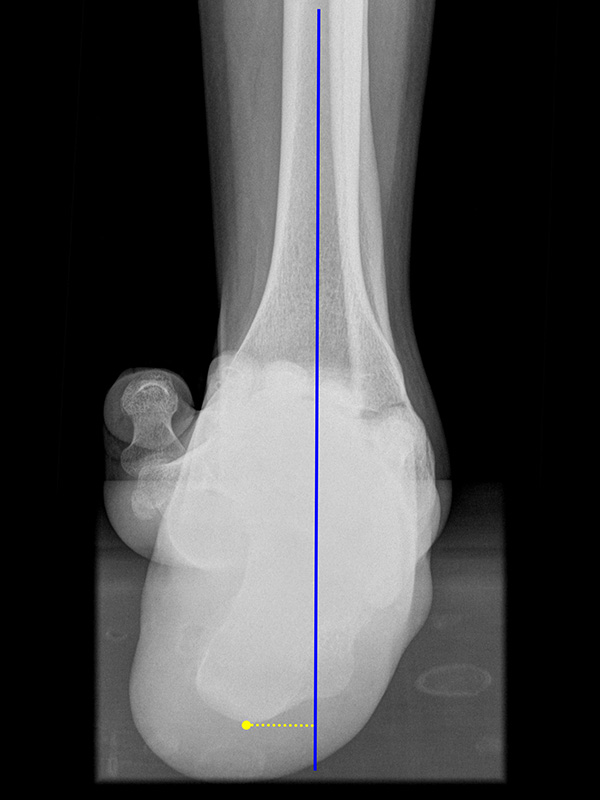

Saltzman Rückfußachsaufnahme (Hindfoot alignment view)

Rückfuß-Alignement-Aufnahmen sind eine wichtige Ergänzung zur Diagnostik von Kalkaneusfehlstellungen (Varus und Valgus), sowie bei der Planung von Rückfußkorrekturen 14.

Indikation:

• Beurteilung der Rückfußachse.

Positionierung:

• Der Patient steht auf einem Podest, beide Beine sind gleichmäßig belastet.

• Die Fußachse ist entlang des Zentralstrahls ausgerichtet.

• Die Röntgenröhre befindet sich dorsal des Beines.

• Röntgenkassette 20° gekippt zur Vertikalen, im 90°-Winkel zum Zentralstrahl.

• Der Zentralstrahl ist von dorsal auf das obere Sprunggelenk fokussiert.

Kennzeichen des Röntgenbildes:

• Markieren der Tibiaachse mit Verlängerung nach distal.

• Der funktionelle Hebelarm des Kalkaneus errechnet sich aus der Distanz zwischen der Tibiaachse und dem am weitesten plantar gelegenen Punkt des Kalkaneus.

• Liegt der tiefste Punkt des Kalkaneus medial der Tibiaachse, handelt es sich um eine Varus-Stellung, liegt er lateral, um eine Valgus-Stellung.

• Norm: Auftrittspunkt 3,2 ± 8 mm medial der Tibiaachse 14.